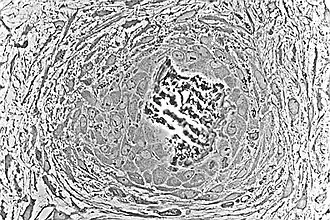

![]() Osteoblasts (purple) rimming a bony spicule (pink - on diagonal of image). In this routinely fixed and decalcified (bone mineral removed) tissue, the osteoblasts have retracted and are separated from each other and from their underlying matrix. In living bone, the cells are linked by tight junctions and gap junctions, and integrated with underlying osteocytes and matrix H&E stain. | |

Morphology and histological staining

Hematoxylin and eosin staining (H&E) shows that the cytoplasm of active osteoblasts is slightly basophilic due to the substantial presence of rough endoplasmic reticulum. The active osteoblast produces substantial collagen type I. About 10% of the bone matrix is collagen with the balance mineral.[29] The osteoblast's nucleus is spherical and large. An active osteoblast is characterized morphologically by a prominent Golgi apparatus that appears histologically as a clear zone adjacent to the nucleus. The products of the cell are mostly for transport into the osteoid, the non-mineralized matrix. Active osteoblasts can be labeled by antibodies to Type-I collagen, or using naphthol phosphate and the diazonium dye fast blue to demonstrate alkaline phosphatase enzyme activity directly.

Light micrograph of decalcified cancellous bone displaying osteoblasts actively synthesizing osteoid, containing two osteocytes -

Light micrograph of undecalcified tissue displaying osteoblasts actively synthesizing osteoid (center) -

Light micrograph of undecalcified tissue displaying osteoblasts actively synthesizing rudimentary bone tissue (center) -

Osteoblasts lining bone (H&E stain)